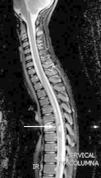

Caso clínicoNiño de 10 años, sin antecedentes y normal desarrollo psicomotor. Presenta empeoramiento del estreñimiento habitual, dolor abdominal e imposibilidad para la micción en las últimas 24h; con anestesia del pie derecho, aparición progresiva de parestesias en extremidad inferior derecha (EID) y dificultad progresiva para la deambulación. Exploración: debilidad y disminución del tono en EID. Hemograma y bioquímica sanguíneas con LDH, las radiografías abdominal y de columna lumbar, y la TAC abdómino-pélvica fueron normales. Con sospecha de mielopatía compresiva, y ante progresión de la debilidad en EID, con imposibilidad para la deambulación, se realiza RM medular, donde se aprecia lesión tumoral en T7 (fig. 1). Se inicia tratamiento con dexametasona intravenosa a dosis altas, progresando la debilidad a la otra extremidad, y se decide realizar cirugía descompresiva medular; previo a esta, la RM cráneo-medular muestra múltiples lesiones compatibles con cavernomas (fig. 2).

La lesión medular es resecada completamente, y su análisis confirma un cavernoma. Reanamnesiando, se nos refiere que en una TAC realizada a la madre 22 años antes, se le dijo que presentaba múltiples lesiones, sin poder precisar su naturaleza, permaneciendo asintomática.

La evolución fue satisfactoria, con recuperación progresiva de la función vesical, fuerza en EID y la deambulación autónoma. La RM cerebral materna confirmó la CM. El estudio genético en nuestro paciente, demostró una mutación en CCM1/KRIT1, en heterocigosis, c.418 C>T, que produce un cambio en la pauta de lectura que da lugar a la aparición de un codón STOP (p.Arg140*). No descrito previamente.